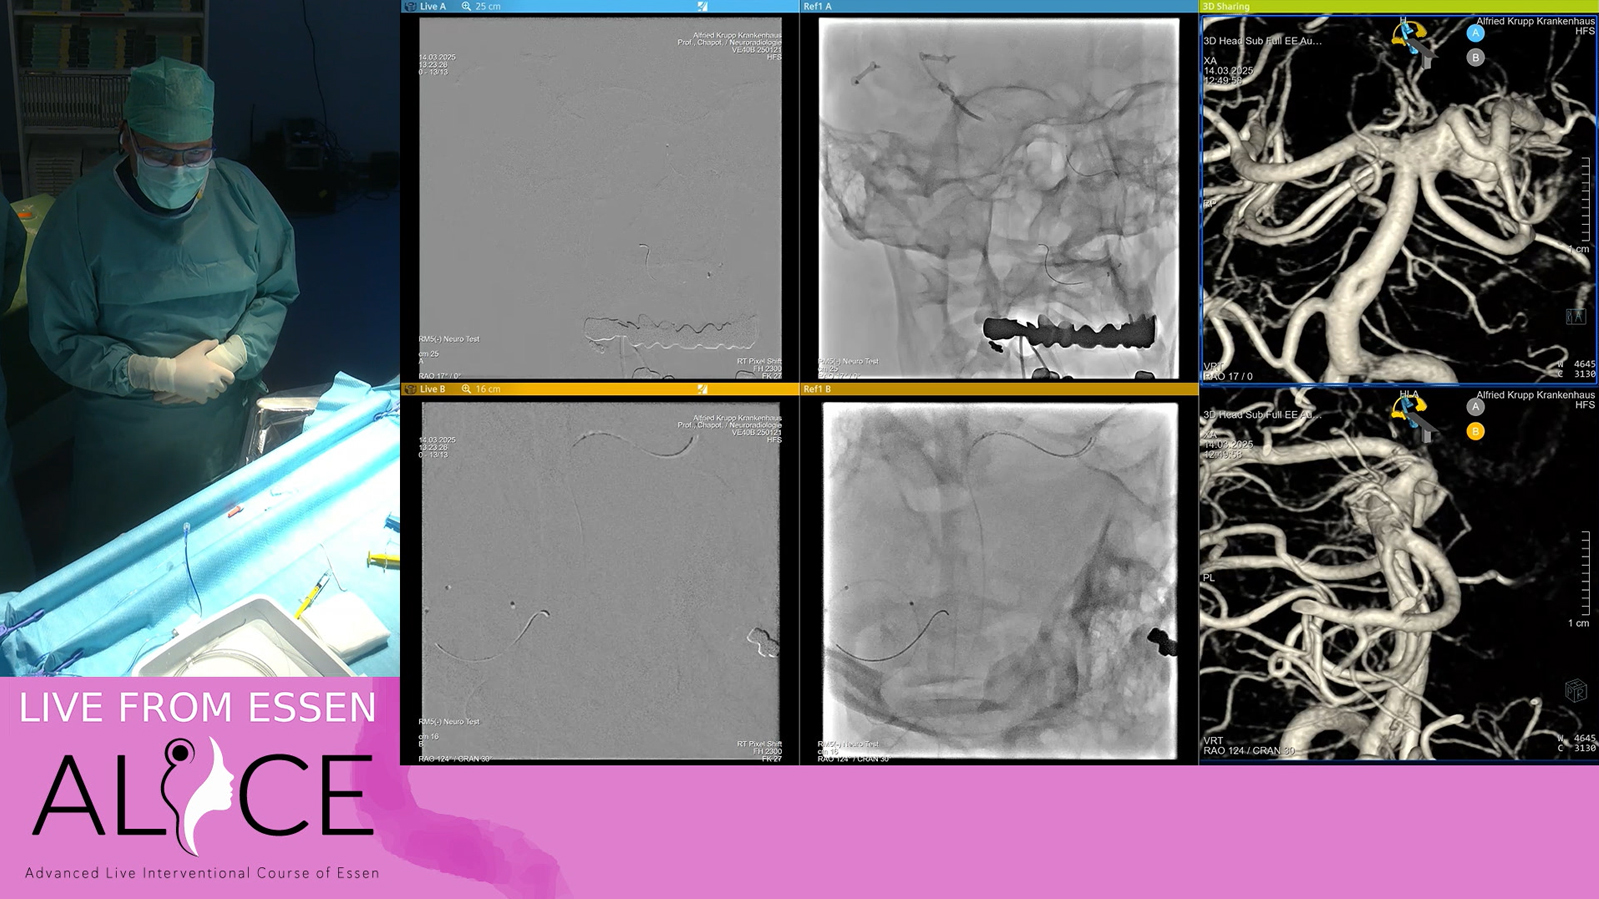

Large distal fusiform MCA aneurysm

from Essen: AVM treated by TVE